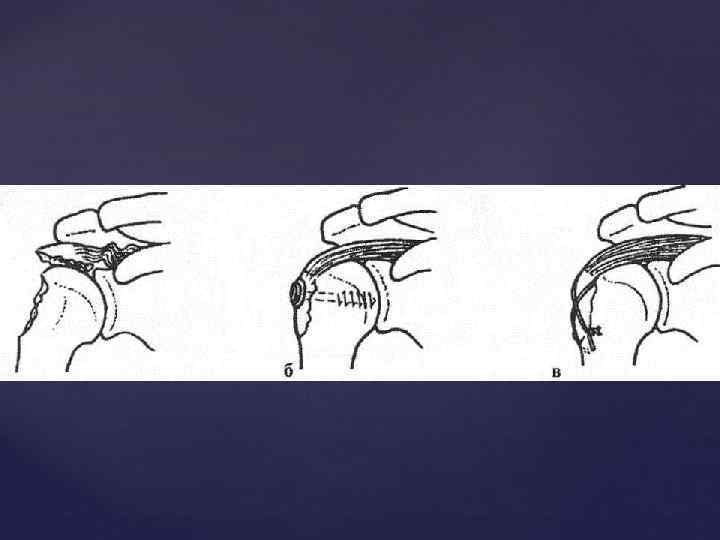

Головка плечевой кости в задней проэкции с вытянутой вдоль туловища конечностью, своей нижнемедиальной частью наслаивается на суставную впадину лопатки и проэцируется всегда выше нижней границы ее. Знание этой ретнгенологической нормы помогает распознать вывихи.

Головка плечевой кости в задней проэкции с вытянутой вдоль туловища конечностью, своей нижнемедиальной частью наслаивается на суставную впадину лопатки и проэцируется всегда выше нижней границы ее. Знание этой ретнгенологической нормы помогает распознать вывихи.

ПЛЕЧЕВОЙ СУСТАВ - появление двух т. о. в головке плечевой кости - 9 -12 мес - син-ие всех т. о в единую головку – 5 -8 лет - син-ие эпифиза и диафиза - 20 -23 года - появление множественных т. о. по краю суставной впадины лопатки – 4, 5 -5 лет - син-ие т. о. края суставной впадины – 67 лет

ПЛЕЧЕВОЙ СУСТАВ - появление двух т. о. в головке плечевой кости - 9 -12 мес - син-ие всех т. о в единую головку – 5 -8 лет - син-ие эпифиза и диафиза - 20 -23 года - появление множественных т. о. по краю суставной впадины лопатки – 4, 5 -5 лет - син-ие т. о. края суставной впадины – 67 лет